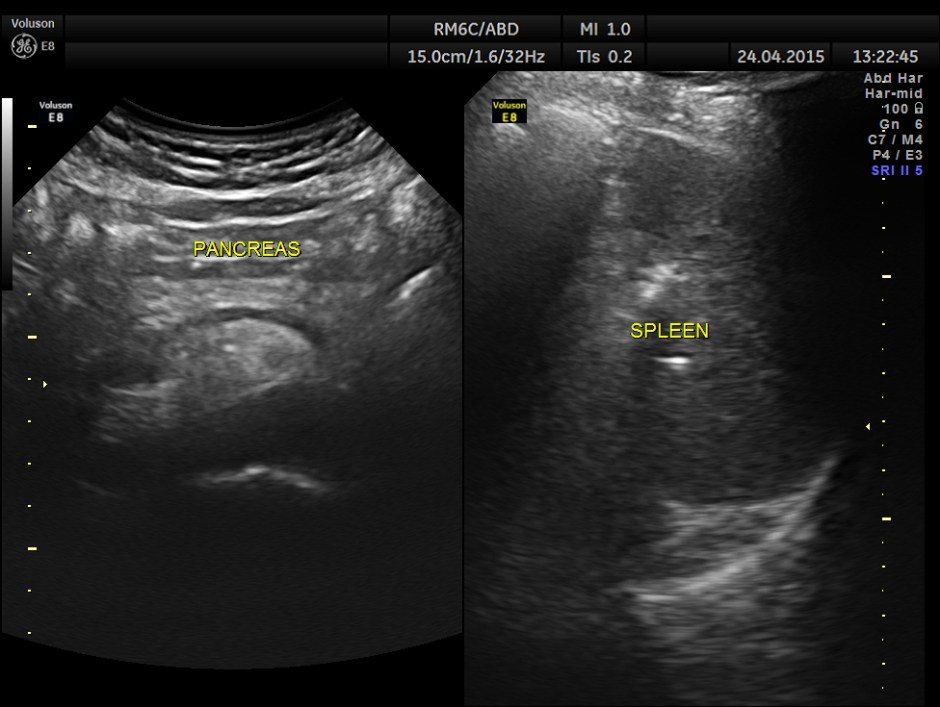

His ultrasound at present showed :